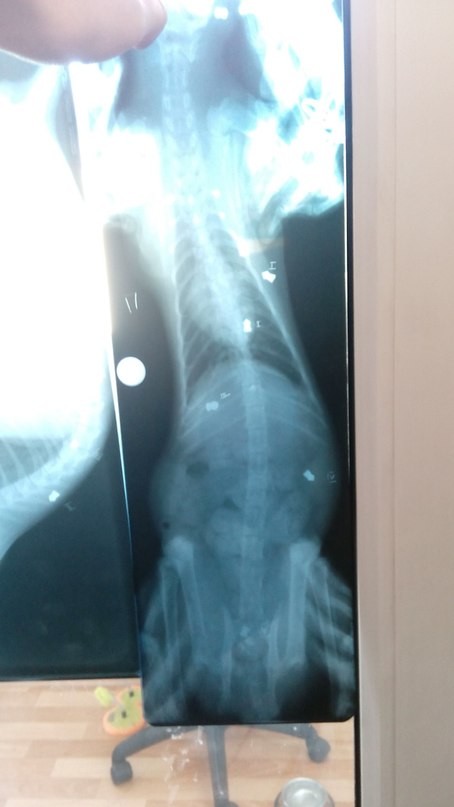

"В теле котёнка было обнаружено 9 пуль. Но, несмотря на боль, кот смог доползти к частному дому за помощью, где его подобрали неравнодушные люди. Сегодня коту будет проведена операция, которая решит его судьбу", — пояснила Екатерина